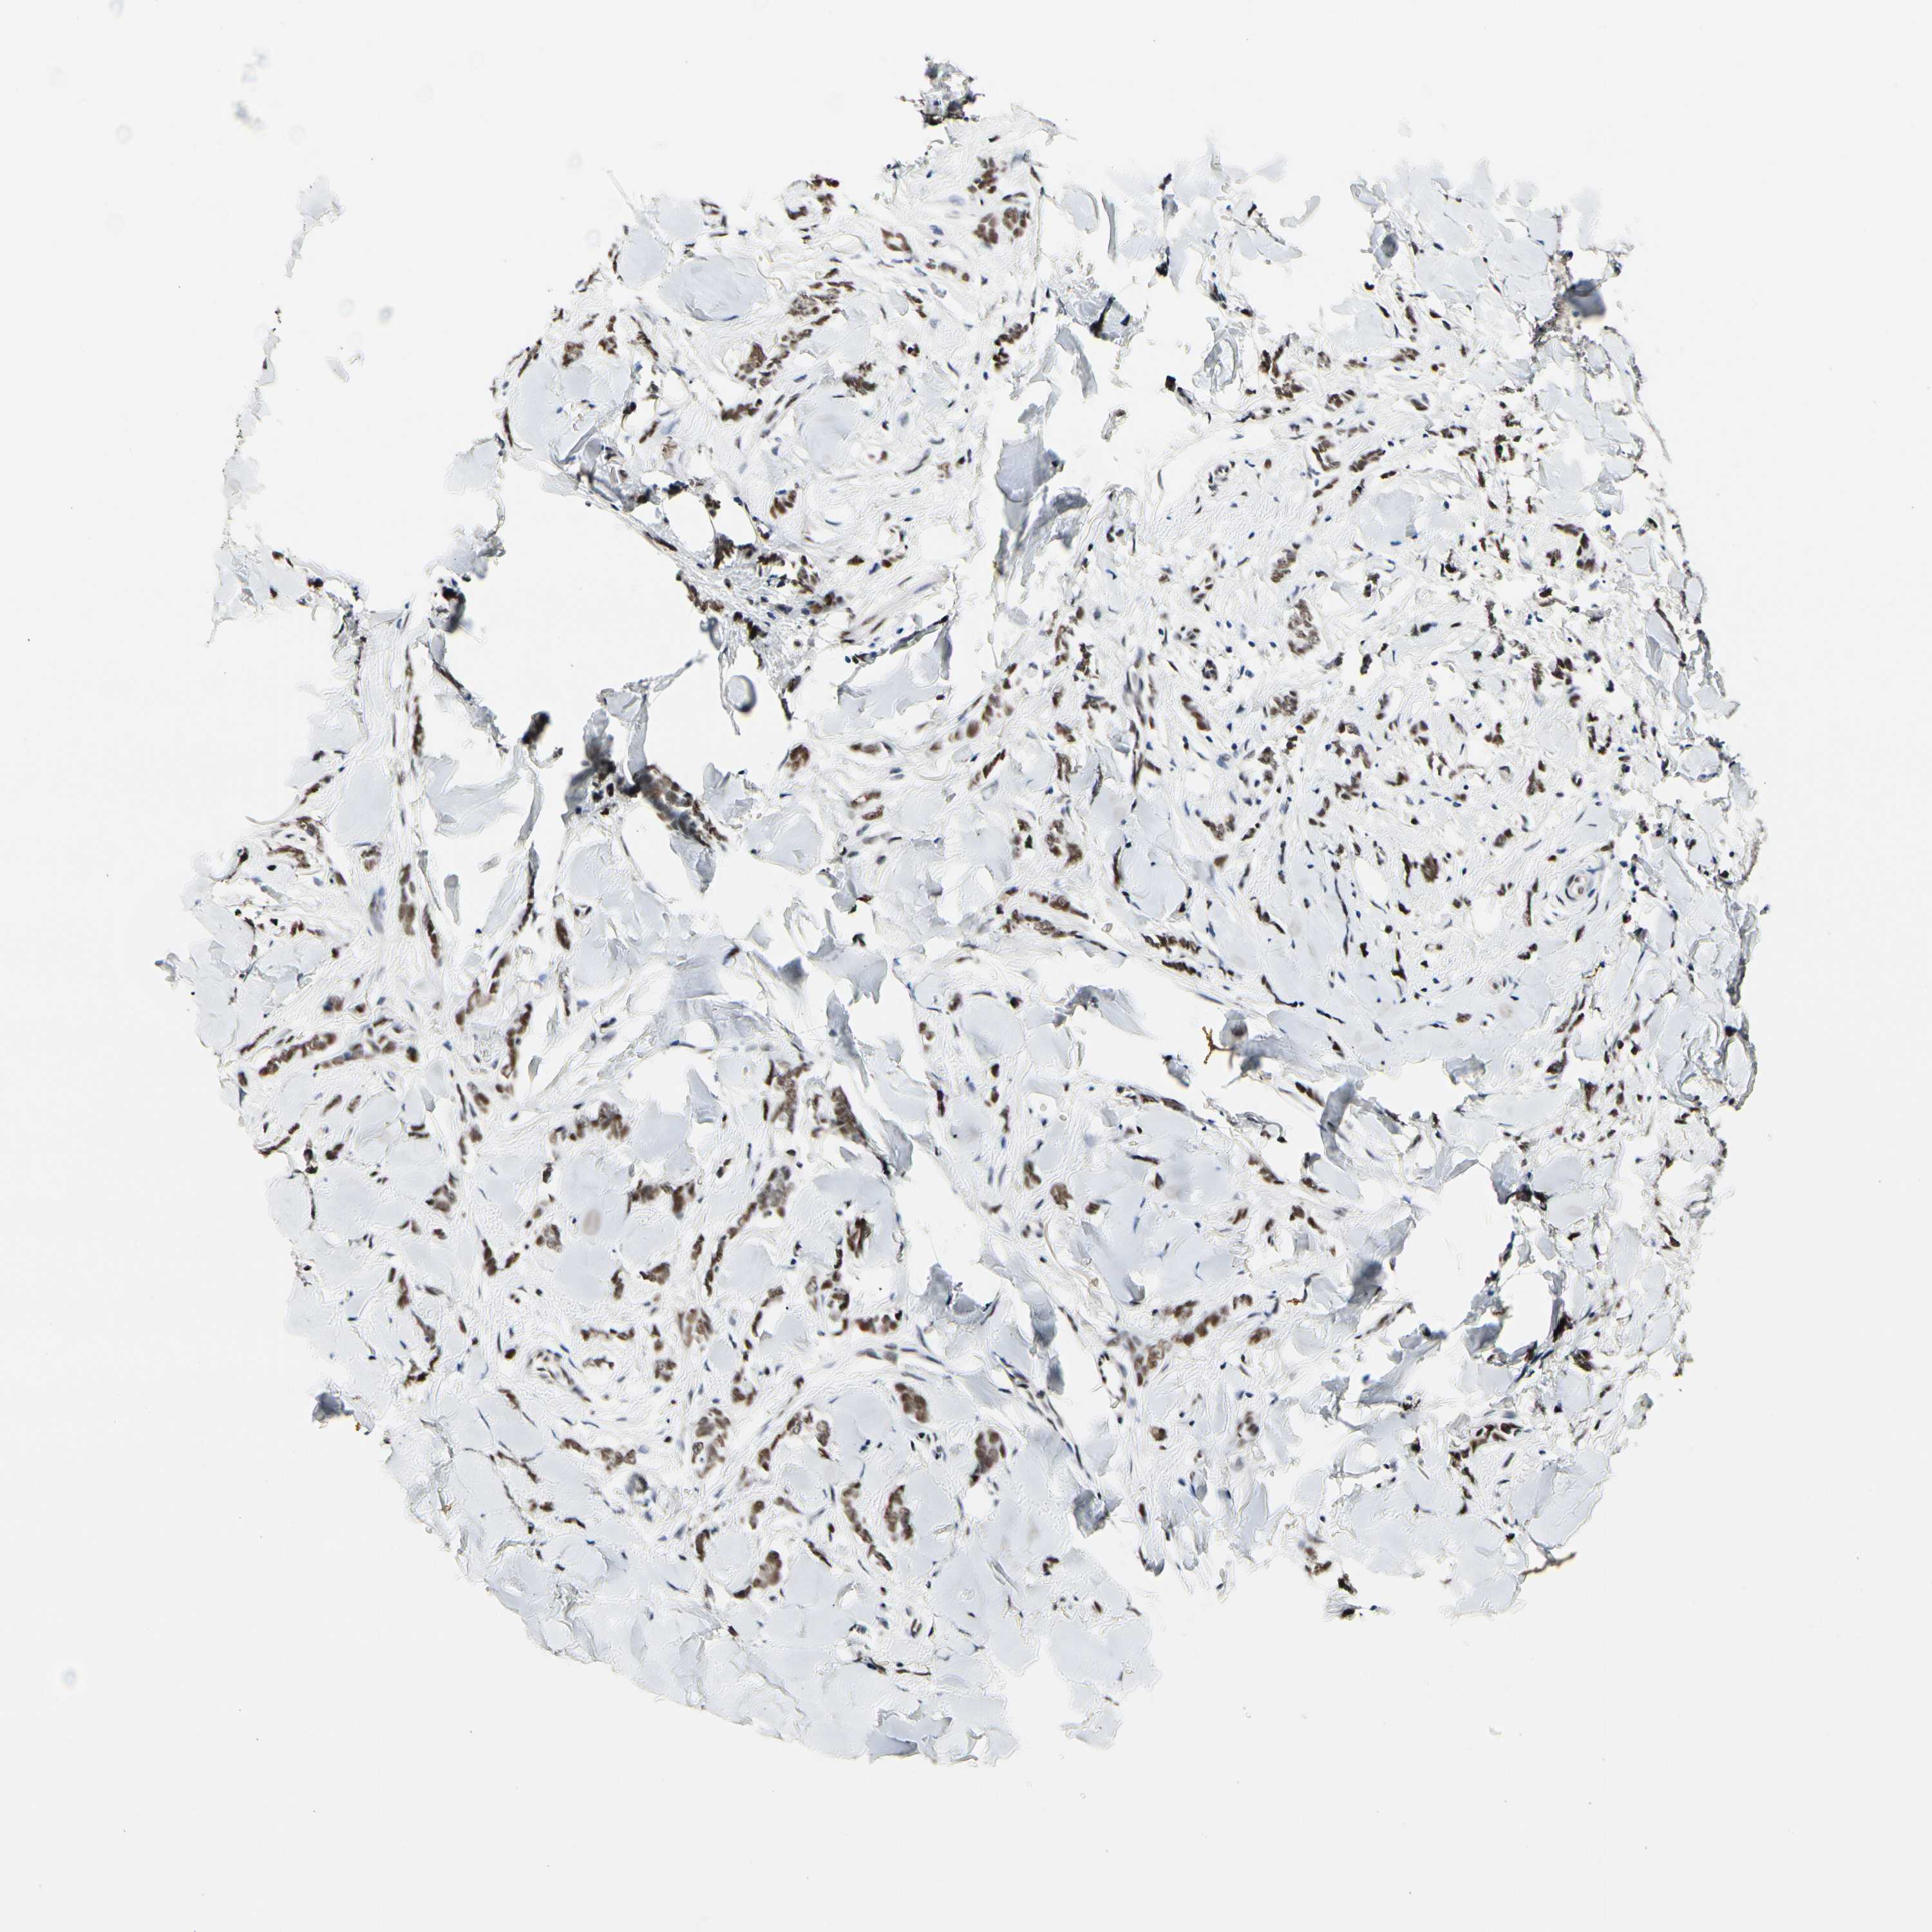

CANCER BREAST CANCER Show tissue menu

BRCA TCGA BRCA VALIDATION PROTEIN EXPRESSION

Breast cancer

Human cancer